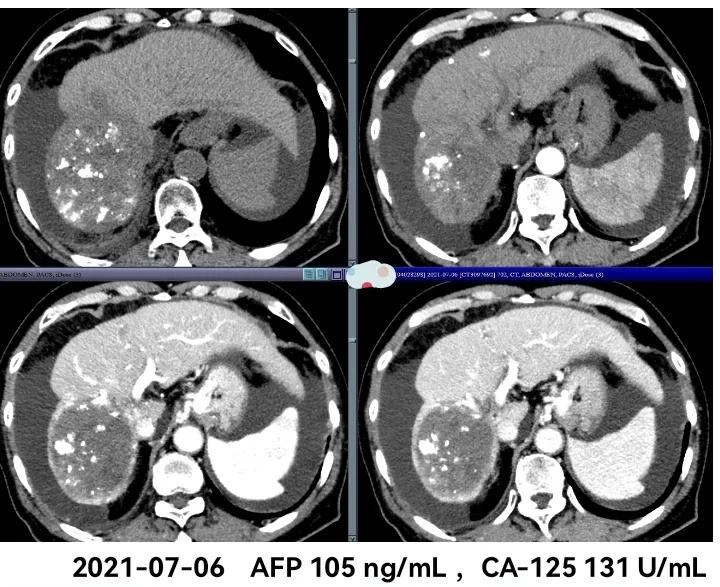

影像学检查:

治疗过程中肿瘤标记物甲胎蛋白(AFP)的变化

这例患者右肝巨大肝癌(直径达17公分)伴肝内多发子灶,且既往已在当地接受过两次介入(TACE)治疗,当地医生可能是担心肝功能衰竭的风险,TACE只是"意思"了一下,所以效果不是很理想。我们经过4次介入(TACE),并联合当时肝癌唯一的一线治疗的分子靶向药物索拉非尼半剂量(2片/天)口服后,肝内肿瘤明显缩小,子灶也明显减少了,生存期也明显延长,目前已达42个月。虽然后一阶段也尝试免疫治疗锦上添花,但4次PD-1治疗后并没有达到预期效果,所以停用。(个人觉得免疫有效的话,大部分都是起效非常快的,4次治疗还没有效果的话,再用下去只会增加免疫相关不良反应,几乎不太可能扭转局面,除非有其他的局部治疗改变了体内的免疫微环境。)日本Kudo教授的这篇TACTICS研究也非常成功的证实了TACE联合靶向治疗肝癌的协同作用,也慢慢改变了很多人对肝癌分子靶向治疗的认识。当然,国内外肿瘤领域的专家学者还在不断研究探索肝癌更加有效的治疗方案,期待更多的治疗方案为肝癌患者带来更好的生存获益。